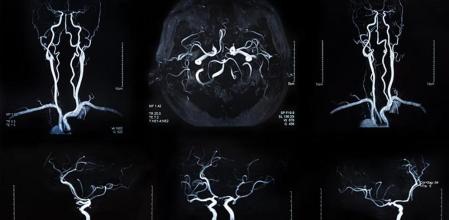

Para facilitar el diagnóstico se solicitarán: análisis de sangre, pruebas de coagulación, electrocardiograma, tomografía computerizada, resonancia magnética y un estudio del flujo sanguíneo cerebral. También se examinarán los trastornos del movimiento, habla, vista, etcétera.